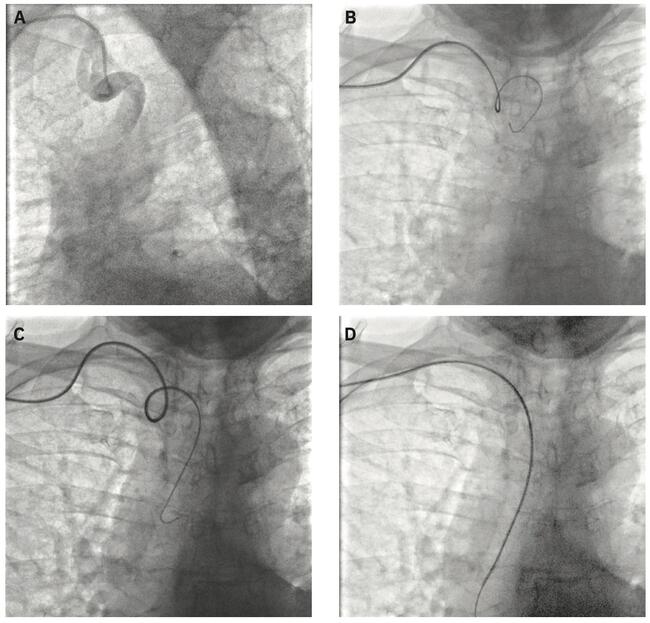

Radial Access Management of Tortuous Brachiocephalic Artery During STEMI Involving Anomalous Right Coronary Artery

This patient is a 78-year female, a former smoker, with a medical history of hypertension, diabetes mellitus type II, peripheral artery disease, and chronic kidney disease with a creatinine baseline of 1.7. She presented to the emergency department (ED) with new-onset chest pain that began as “on and off” for 3 days, but became significantly worse 1 hour before presenting to the ED. Upon arriving to the ED, she was chest-pain free and her electrocardiogram (EKG) (Figure 1) showed normal sinus rhythm with Q wave in the inferior leads. After 15 minutes of presentation, she started having chest pain and a repeat EKG was done (Figure 2) that showed ST elevation in the inferior leads. A ST-elevation myocardial infarction (STEMI) code was activated, and patient was taken to the catherization lab for cardiac catherization.